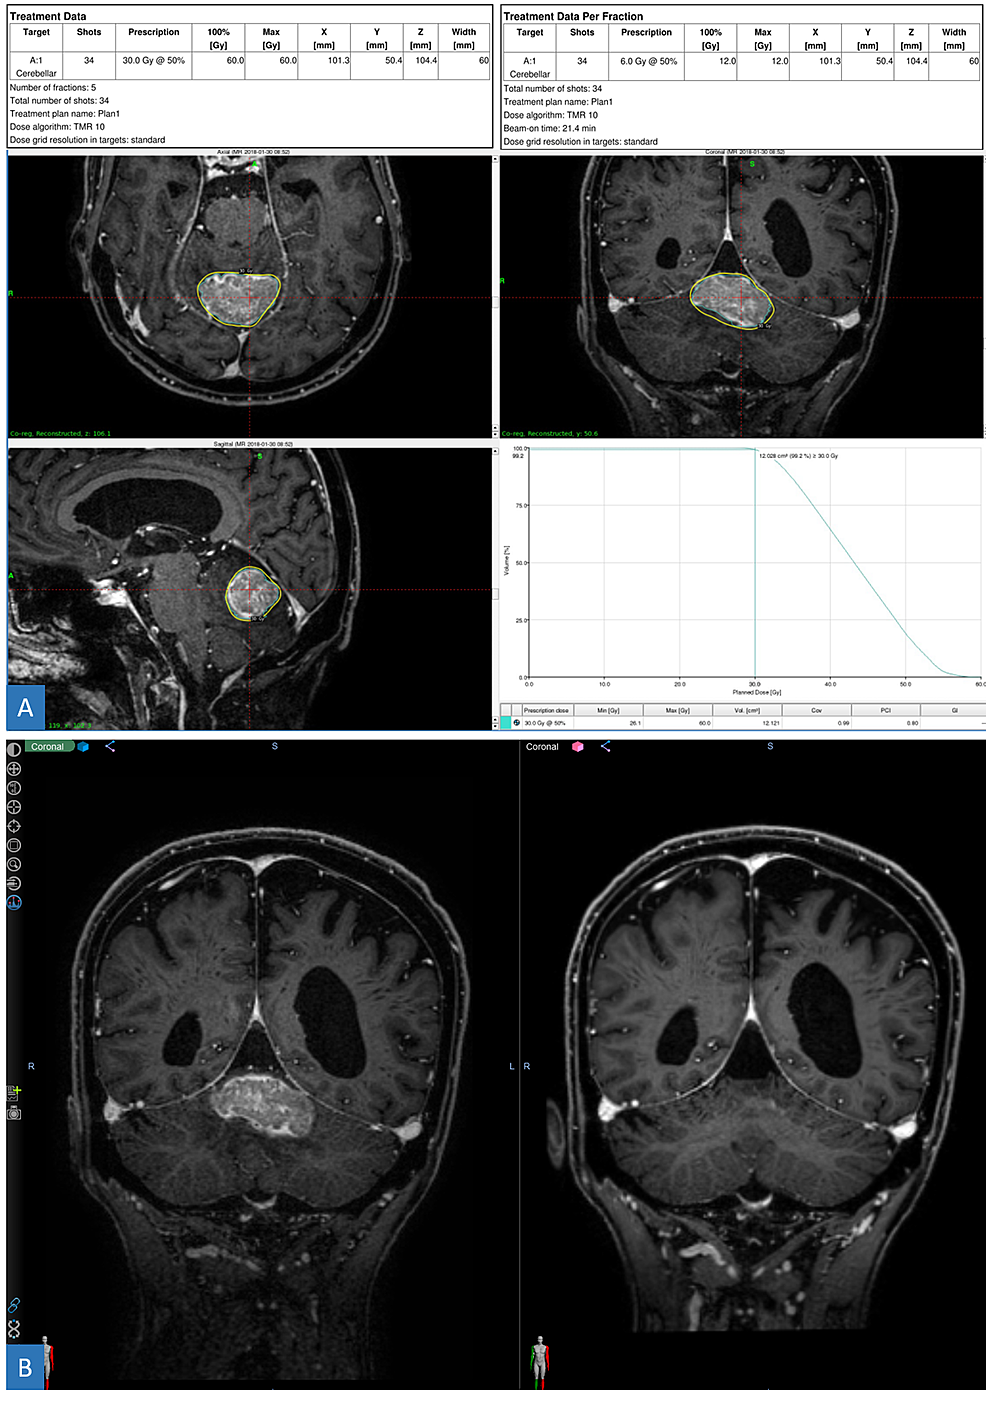

Patient history timeline, GK SRS treatment plans, and tumor response to Gk Radiosurgery — stereotactic radiosurgery of multiple brain metastases: — mechanistically, gk converges radiation beams from ~ 200 fixed cobalt sources on the target while linac. what is gamma knife radiosurgery? It’s also called stereotactic radiosurgery. The gk system consists of an. — the gamma knife icon™ (gk icon™) is the most recent model available from elekta, providing. Gk Radiosurgery.